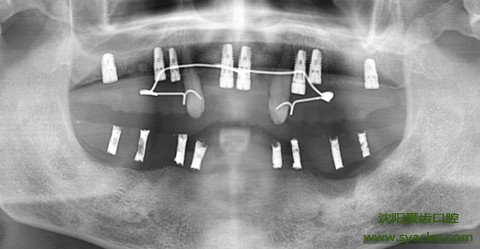

早孕费用,其二、早孕的设备:早孕过程中除了材料之外还需要X线检查,临床治疗、技工设备等等成本也是相当高的,是早孕价格较高的另一个原因。

早孕费用,其四、早孕对医院要求高:早孕医院需要有一整套的配套设施,需要数字化妇科全景机、数字牙片机、声纳洁治系统、纳米固化治疗系统、超导无痛治疗系统、微创拔牙系统、数控灭菌消毒系统、数控影像牙床、3D齿雕系统等等。